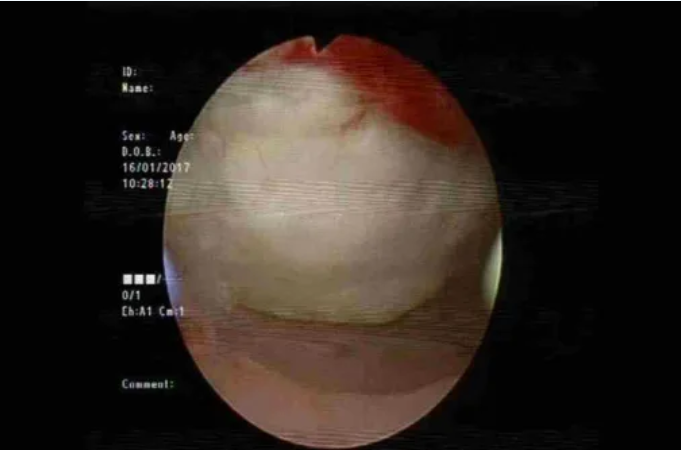

图:宫腔镜显示HIFU造成的子宫内膜损伤(本图由北京复兴医院马宁教授提供)

消融治疗的并发症主要包括过度治疗导致的邻近器官损伤。除影响有生育需求患者的子宫内膜或浆肌层损伤外,还可能损伤肠管(发生率1-3‰)、膀胱、皮肤及皮下组织。其中肠管损伤多为延迟性,发生于消融后5-10天。部分患者可能因血管损伤或子宫出血出现术后大出血。HIFU和微波治疗可能引发皮肤灼伤。神经损伤是HIFU特有的并发症,与靶组织后方的聚焦超声后场能量相关,这也是HIFU治疗中需采用静脉镇静镇痛的原因之一。不过,仍有少数患者出现短暂神经受累,表现为下肢感觉或运动障碍。